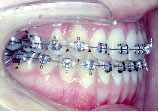

クォードヘリックスで上顎歯列を左右へ拡げた後、右上第1小臼歯を抜歯し、エッジワイズブラケットを付けて術前矯正を始めました。

骨の中に埋まっている左上の第2小臼歯は手術の時に抜いてもらいます。

術前矯正が終わりました。一見きれいになったようですが下あごはまだ左にずれたままです。

手術を担当する口腔外科医と最終打ち合わせをします。